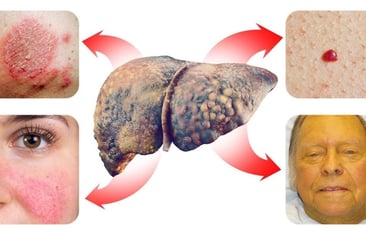

تشمل التغيرات الجلدية المرتبطة بمرض الكبد الدهني اليرقان، وحكة الجلد، والتهاب الجلد، والوردية، والأوردة العنكبوتية، واعتلال الجلد الأسود. يمكن أن تتنوع البقع الجديدة المسطحة أو المرتفعة على الجلد من التبييض إلى الاحمرار.

يمكن أن يظهر مرض الكبد الدهني أيضًا أعراضًا على الوجه، مثل اليرقان، والوردية، والتهاب الجلد، وحكة الجلد، والأوردة العنكبوتية، واسمرار الجلد.

بالنسبة لأعراض الكبد الدهني على الجلد، فهي تشمل:

- اليرقان

- تصبغ الجلد

- كدمات

- تورم

- نتوءات جلدية

- حكة

- أوردة عنكبوتية

- بقع صفراء حول العينين

- راحة اليد